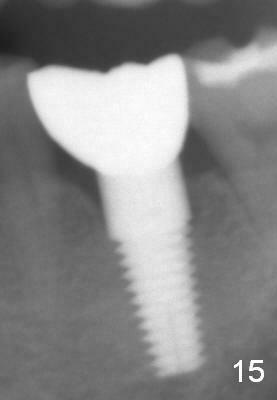

Two and a half months post cementation, the buccal metal show is much less and confined to the midbuccal portion. It appears that the papillae increase their mesiodistal dimension (data not shown). Bone appears to remain stable over the implant surface 2.5 and 9 months post cementation (Fig.12 >,13). The papillae around the implant crown remain normal 11 months post cementation (Fig.14 *). No bone loss is noticed 26 (Fig.15) or 38 (Fig.16) months post cementation. There is no bone loss around the 7x17 mm tissue-level implant 6 years 8 months post cementation (Fig.17).